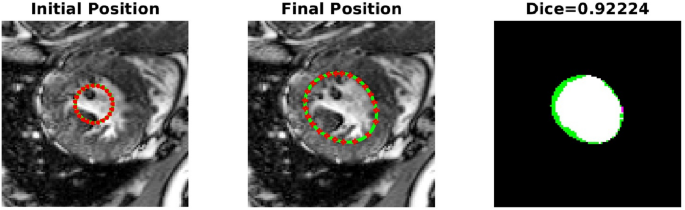

-

TC-2A,TC-2B: In the second case, Figs. 4 and 5 demonstrate the effect of integrating a convexity-preserving loss term in the segmentation of the left ventricle. As depicted in Fig. 4, a purely data-driven segmentation algorithm fails in cases where trabeculae and papillary muscles have comparable intensities to the myocardium. However, by incorporating prior shape information that preserves convexity, PICS is able to accurately segment the left ventricle even in the presence of confusing muscles, as shown in Fig. 5. The inclusion of the shape loss term results in an increase of the Dice score from 0.68 without the shape loss term to 0.92 with it. We also show the segmentation output with traditional Chan–Vese (https://scikit-image.org/docs/stable/auto_examples/segmentation/plot_chan_vese.html) and snake (https://scikit-image.org/docs/stable/auto_examples/edges/plot_active_contours.html) models in Fig. 6. In the level set formulation, the Chan–Vese model does not distinguish between the bright intensities of the left and right ventricle. On the other hand, the traditional snake model, even when initialized very close to the true mask, adheres to locations with sharp pixel gradients.